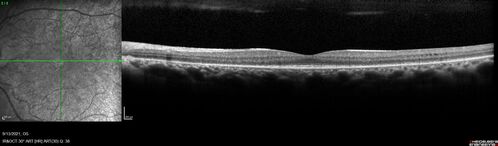

Ocular Lymphoma - Initially presented like auto-immune retinopathy

43 year old man: initial presentation - The vision in the left eye is blurry and opaque for about 2 weeks.  In the central of the vision, when he covers the right eye, in the center of the left eye there is a film with a light in the middle.  This has never happened before.  He has not been sick for the last few months.  A few weeks ago he saw waves on the floor when looking down but that has gone away.  Since the vision loss started the vision has not changed much.  The central vision is not getting better.

VA improved over 2 months to normal.  Then the patient had 2 more episodes of self-limited vision loss (no treatment).  Then 2 years later he presented with a diagnosis of CNS lymphoma and later developed subretinal deposits (last images)